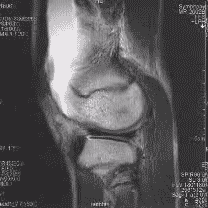

| تصویر امآرآی از مفصل زانو | |